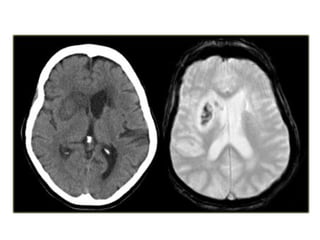

Patient with deep cerebral vein thrombosis , notice the bilateral infarctions in

the basal ganglia

The same patient , there is absence of flow void in the internal

cerebral veins, straight sinus and right transverse sinus (blue

arrows) , on the MRA the right transverse sinus is not visualized